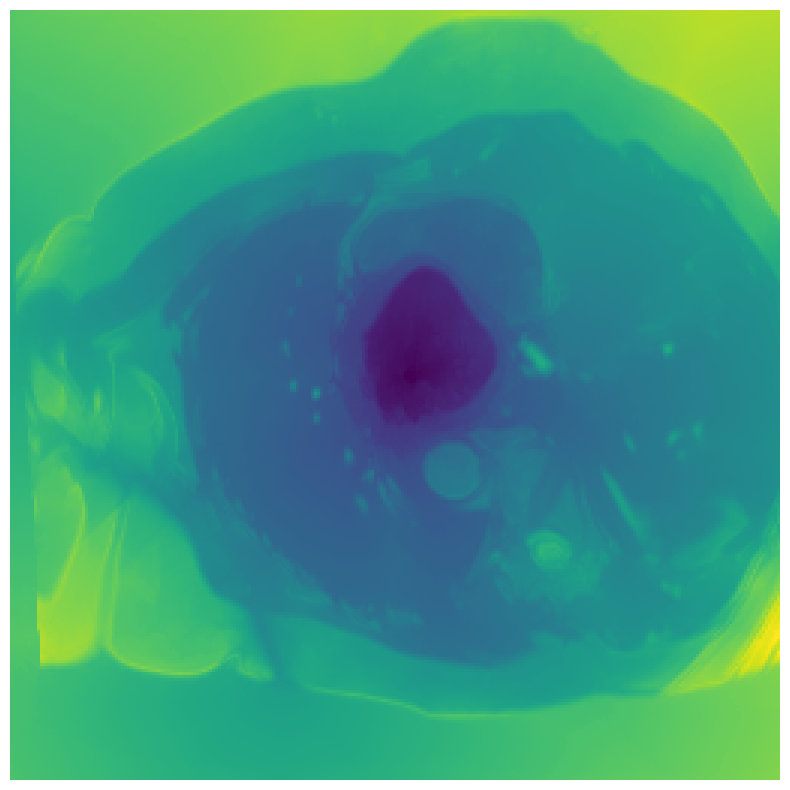

We normalize the volumes and resize the slices to pixels. As the official dataset comes with full annotations, we create a synthetic point ground truth. This is done by first randomly choosing the centers of the point annotations within the class masks, followed by filling an ellipse with axes lengths of and (in pixels) around each center. The intersections of these elliptic discs with the underlying full annotations are then used as our point ground truth. See Figure 2 for an example of the created weak annotation mask. The point annotations are created for every slice, one for each foreground object present in the slice.

5.1 Segmentation of cardiac structures

The average 3D Dice scores and HD95 values on the ACDC test set are given in Table 2, and boxplots in figures 4 and 5 show the distributions. We see that, in terms of DSC, the proposed strategy of using intensity-aware distances withing boundary loss performs better than simply using the Euclidean distance, with the best results achieved by using the strictly intensity based MBD. The HD95 however favors the original version of , which may be do to its smoother predictions and less fragmentation and oversegmentation. The CRF-loss results are significantly worse in both metrics.

In Figure 3 we show the 3D DSC validation curve evolution for a single run. The CRF-loss seems to have converged to a low DSC value, while all settings combining CE and boundary loss reach values close to the full supervision in the beginning of the training and then slowly collapse towards to the point annotations. The MBD version stands out, degrading slower, thus providing a wider range of potentially good models for evaluation.

Qualitative comparison

In Figure 6 we provide qualitative results on a number of randomly chosen test set slices. Upon visual inspection, we can observe that training with the intensity-aware distances (particularly with and ) follows the image gradients better and is better at recovering the underlying shape than the Euclidean version. The CRF-loss seems to recover the shape of the myocardium and left ventricle to some extent, but fails entirely on the right ventricle.